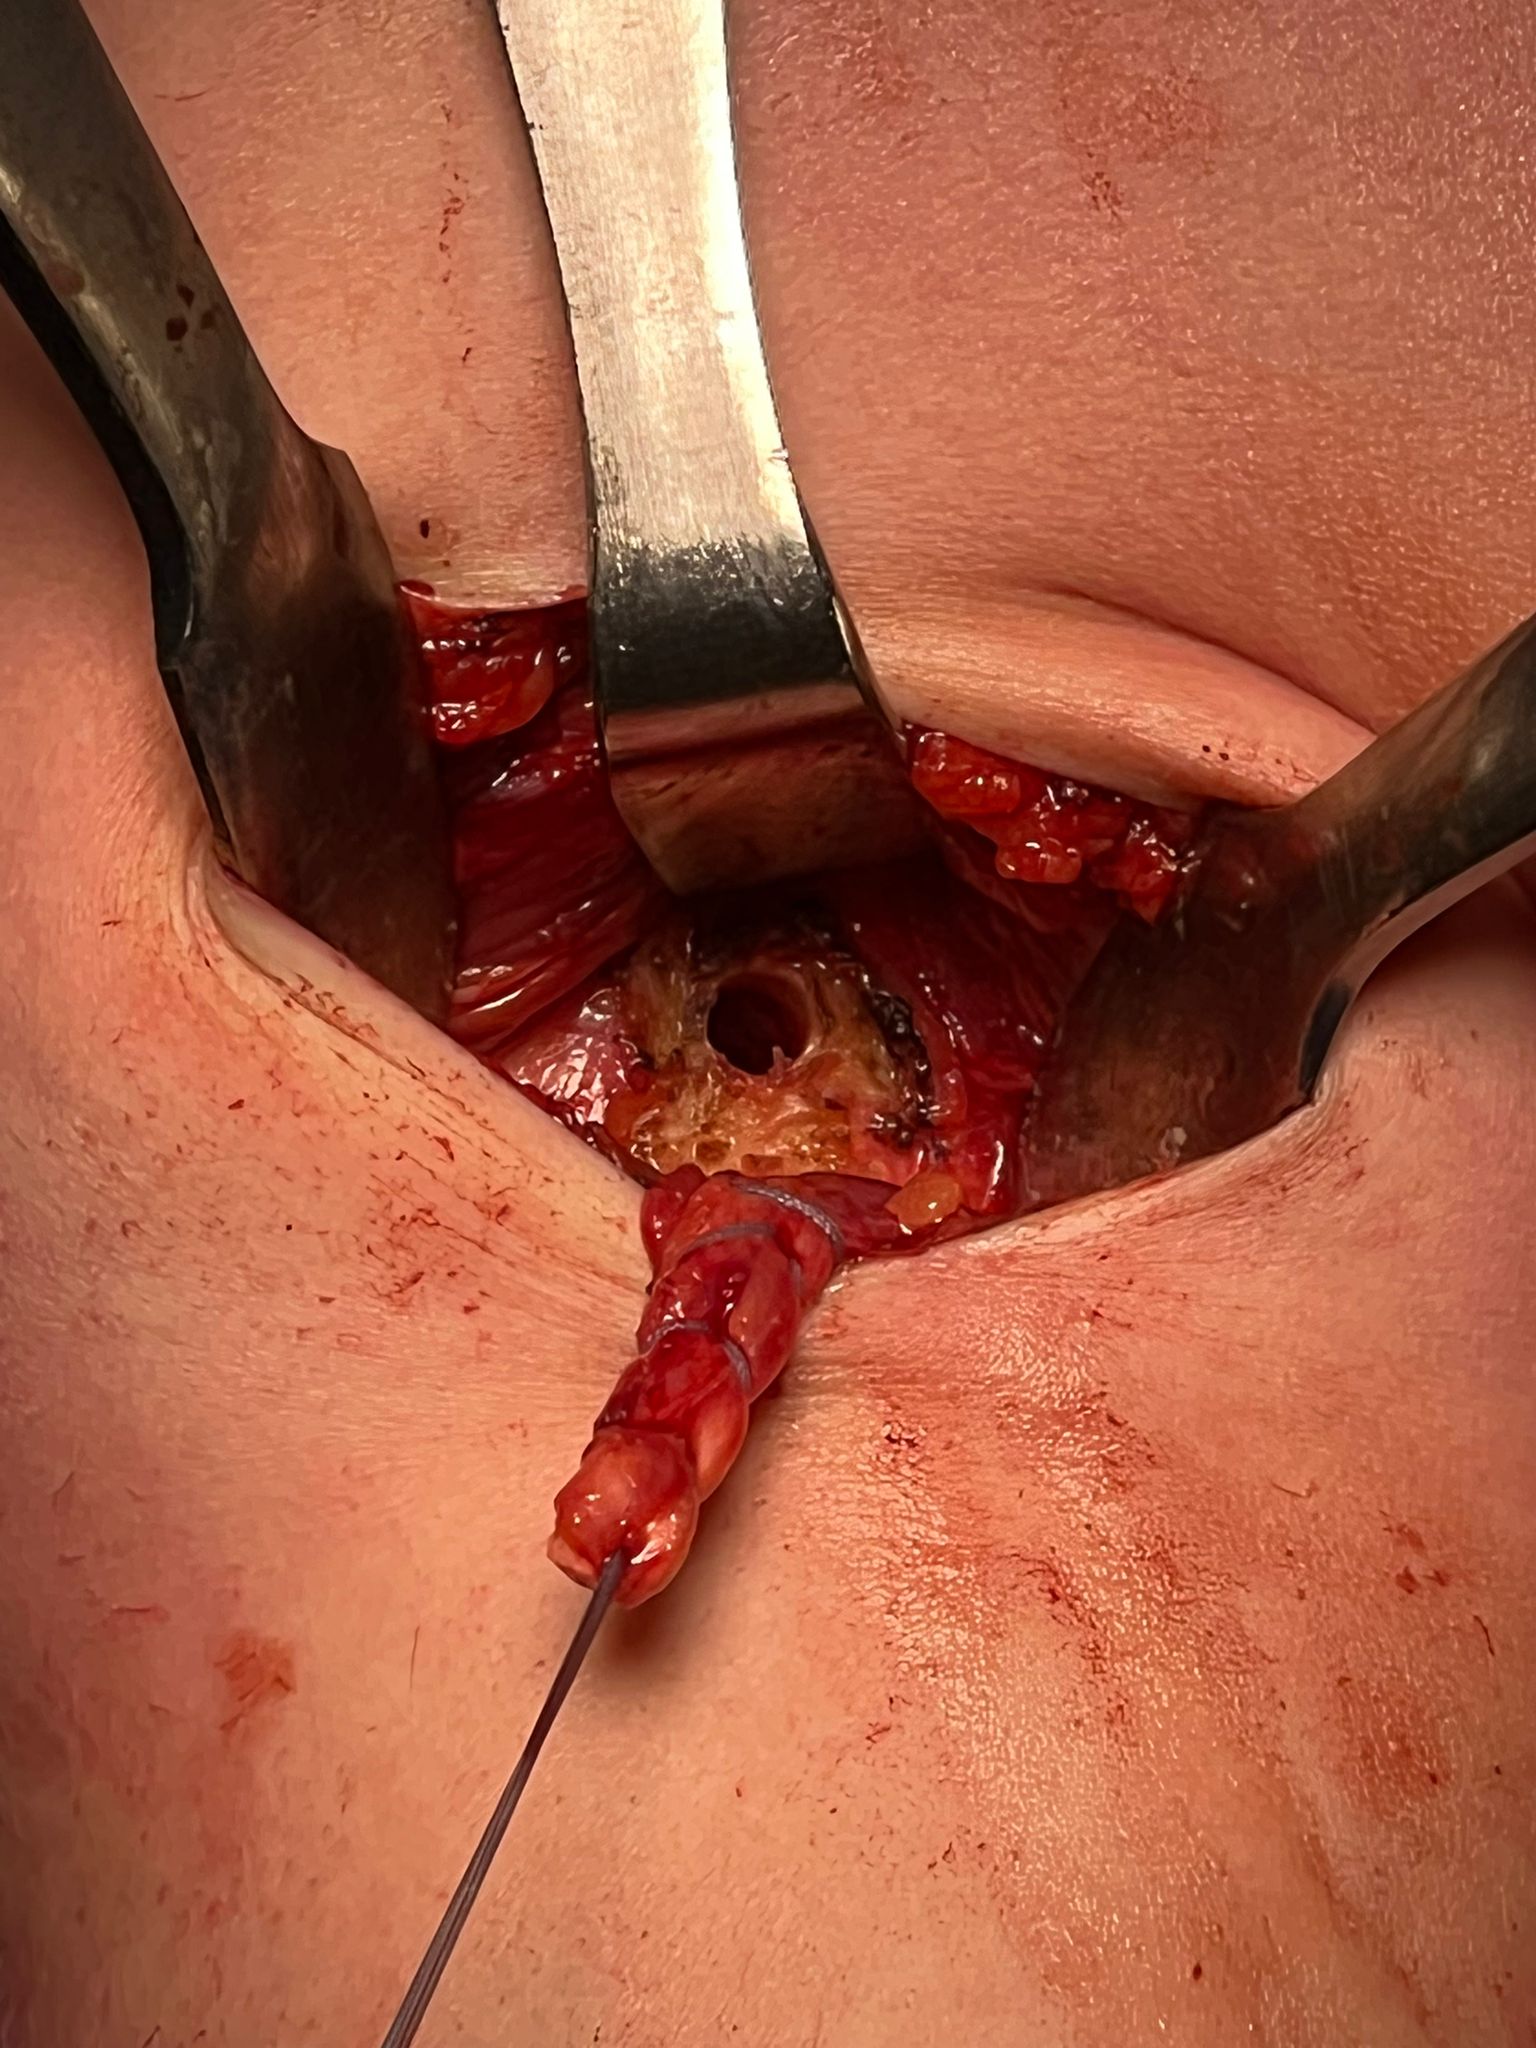

- open approach to biceps

- incision centered on humerus below pectoralis tendon

- retract deltoid laterally / elevate pectoralis tendon / conjoint tendon medially

- find biceps tendon / shorten to 2cm of tendon / suture

- anchor biceps tendon

Bicortical open subpectoral biceps tenodesis using Arthrex Biceps Button